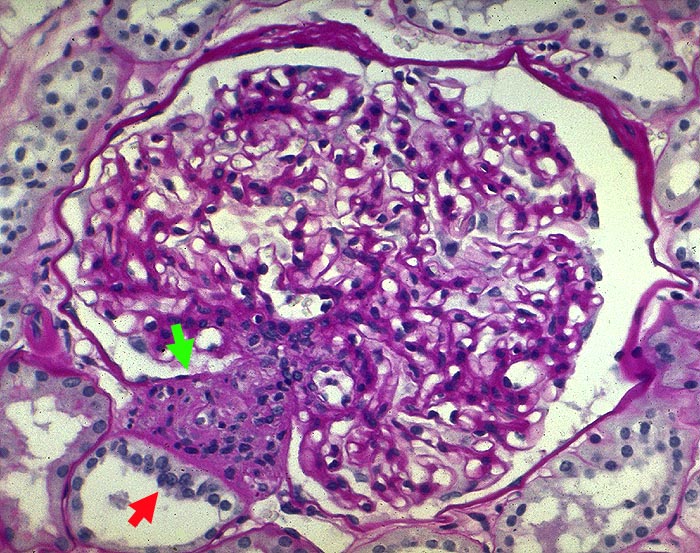

PathoPic ID 1604 - Juxtaglomerulärer Apparat mit Macula densa

Juxtaglomerulärer Apparat mit Macula densa

Normalbefund

Niere

Normaler Glomerulus.

Juxtaglomerulärer Apparat mit

Macula densa. Zartes Mesangium.

Histologie